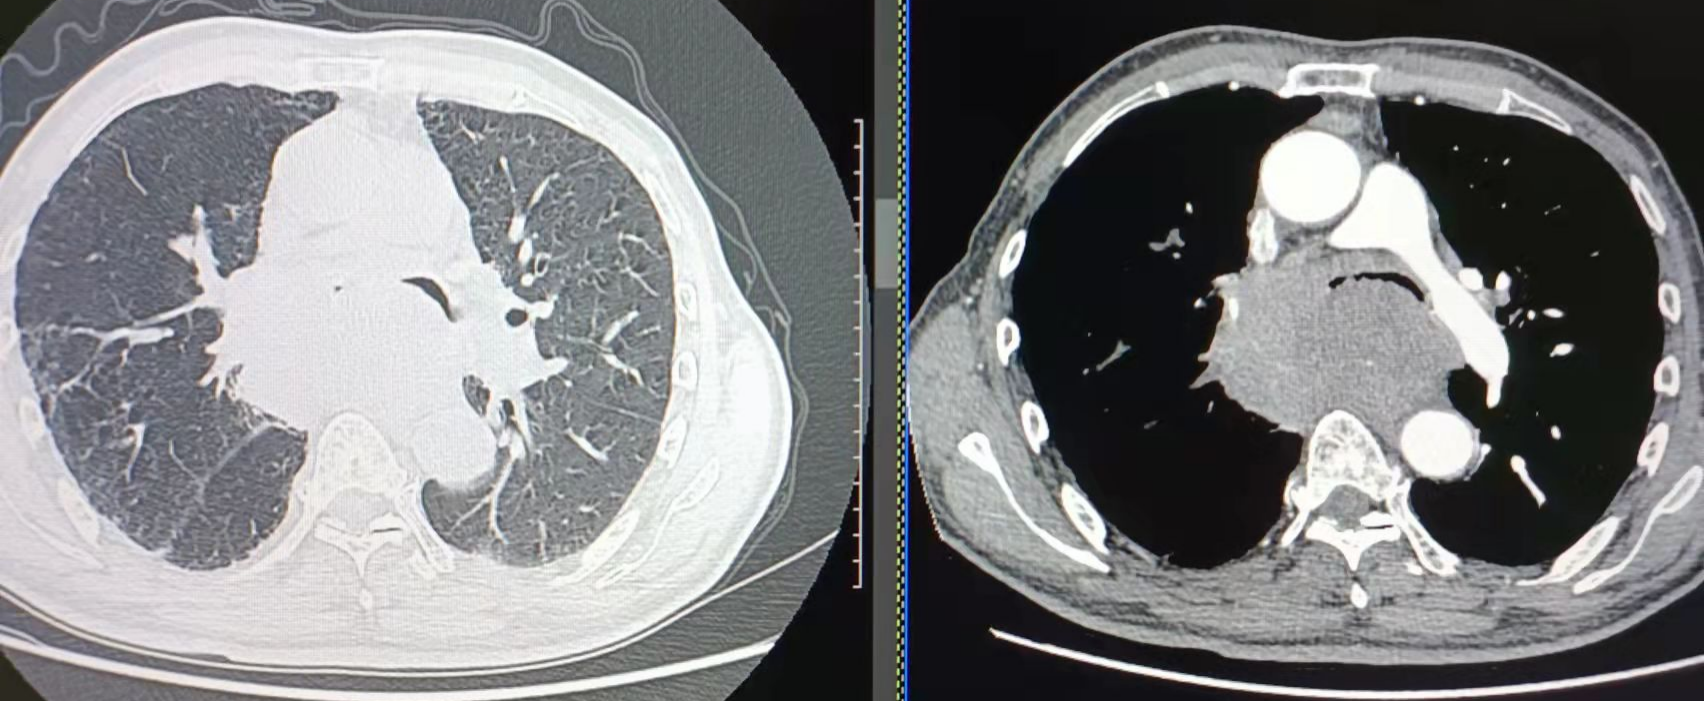

胸部CT示(11-22):气管、左主支气管受压明显变窄,右主支气管几乎完全闭塞。

大气道削瘤术后,患者病情暂时缓解,治疗远未结束,各项后续治疗措施有条不紊地持续推进。在重症医学科里,医务科组织为患者进行了多学科会诊讨论后,陈璞莹主任为患者制定了下一步诊疗方案:左总有肿物长入,右总几乎完全阻塞,需要行双气道支架置入术。但支架需要根据患者气道定制,为了做到严丝合缝,影像科章强主任帮忙测量气道直径大小。

12月6日,定制的支架已到位,呼吸与危重症医学二科介入团队陈璞莹主任、王飞副主任医师再次为患者成功实施全麻后硬镜下行左、右主支气管双支架置入,术后第二天患者成功拔除气管插管,转出重症医学科,转回呼吸与危重症医学二科进行后续治疗。